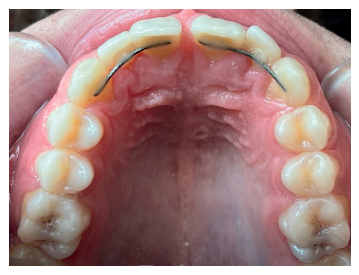

Como prueba complementaria se solicitó un estudio CBCT, en el que se observaron signos de fractura leve de la cortical vestibular en la zona del incisivo central superior derecho, a nivel del tercio medio radicular (Figura 4), por lo que se procedió a realizar la ferulización de todo el sector anterosuperior (Figura 5).